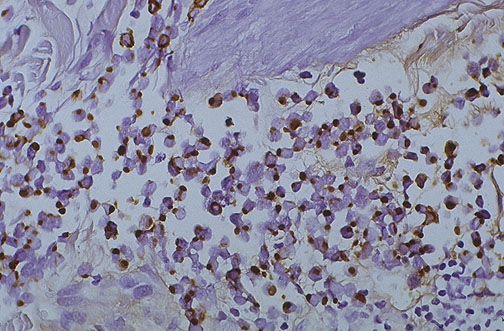

This is an AE-1 positive Merkel cell carcinoma of skin at high power. AE-1 is a cytokeratin marker for carcinomas.